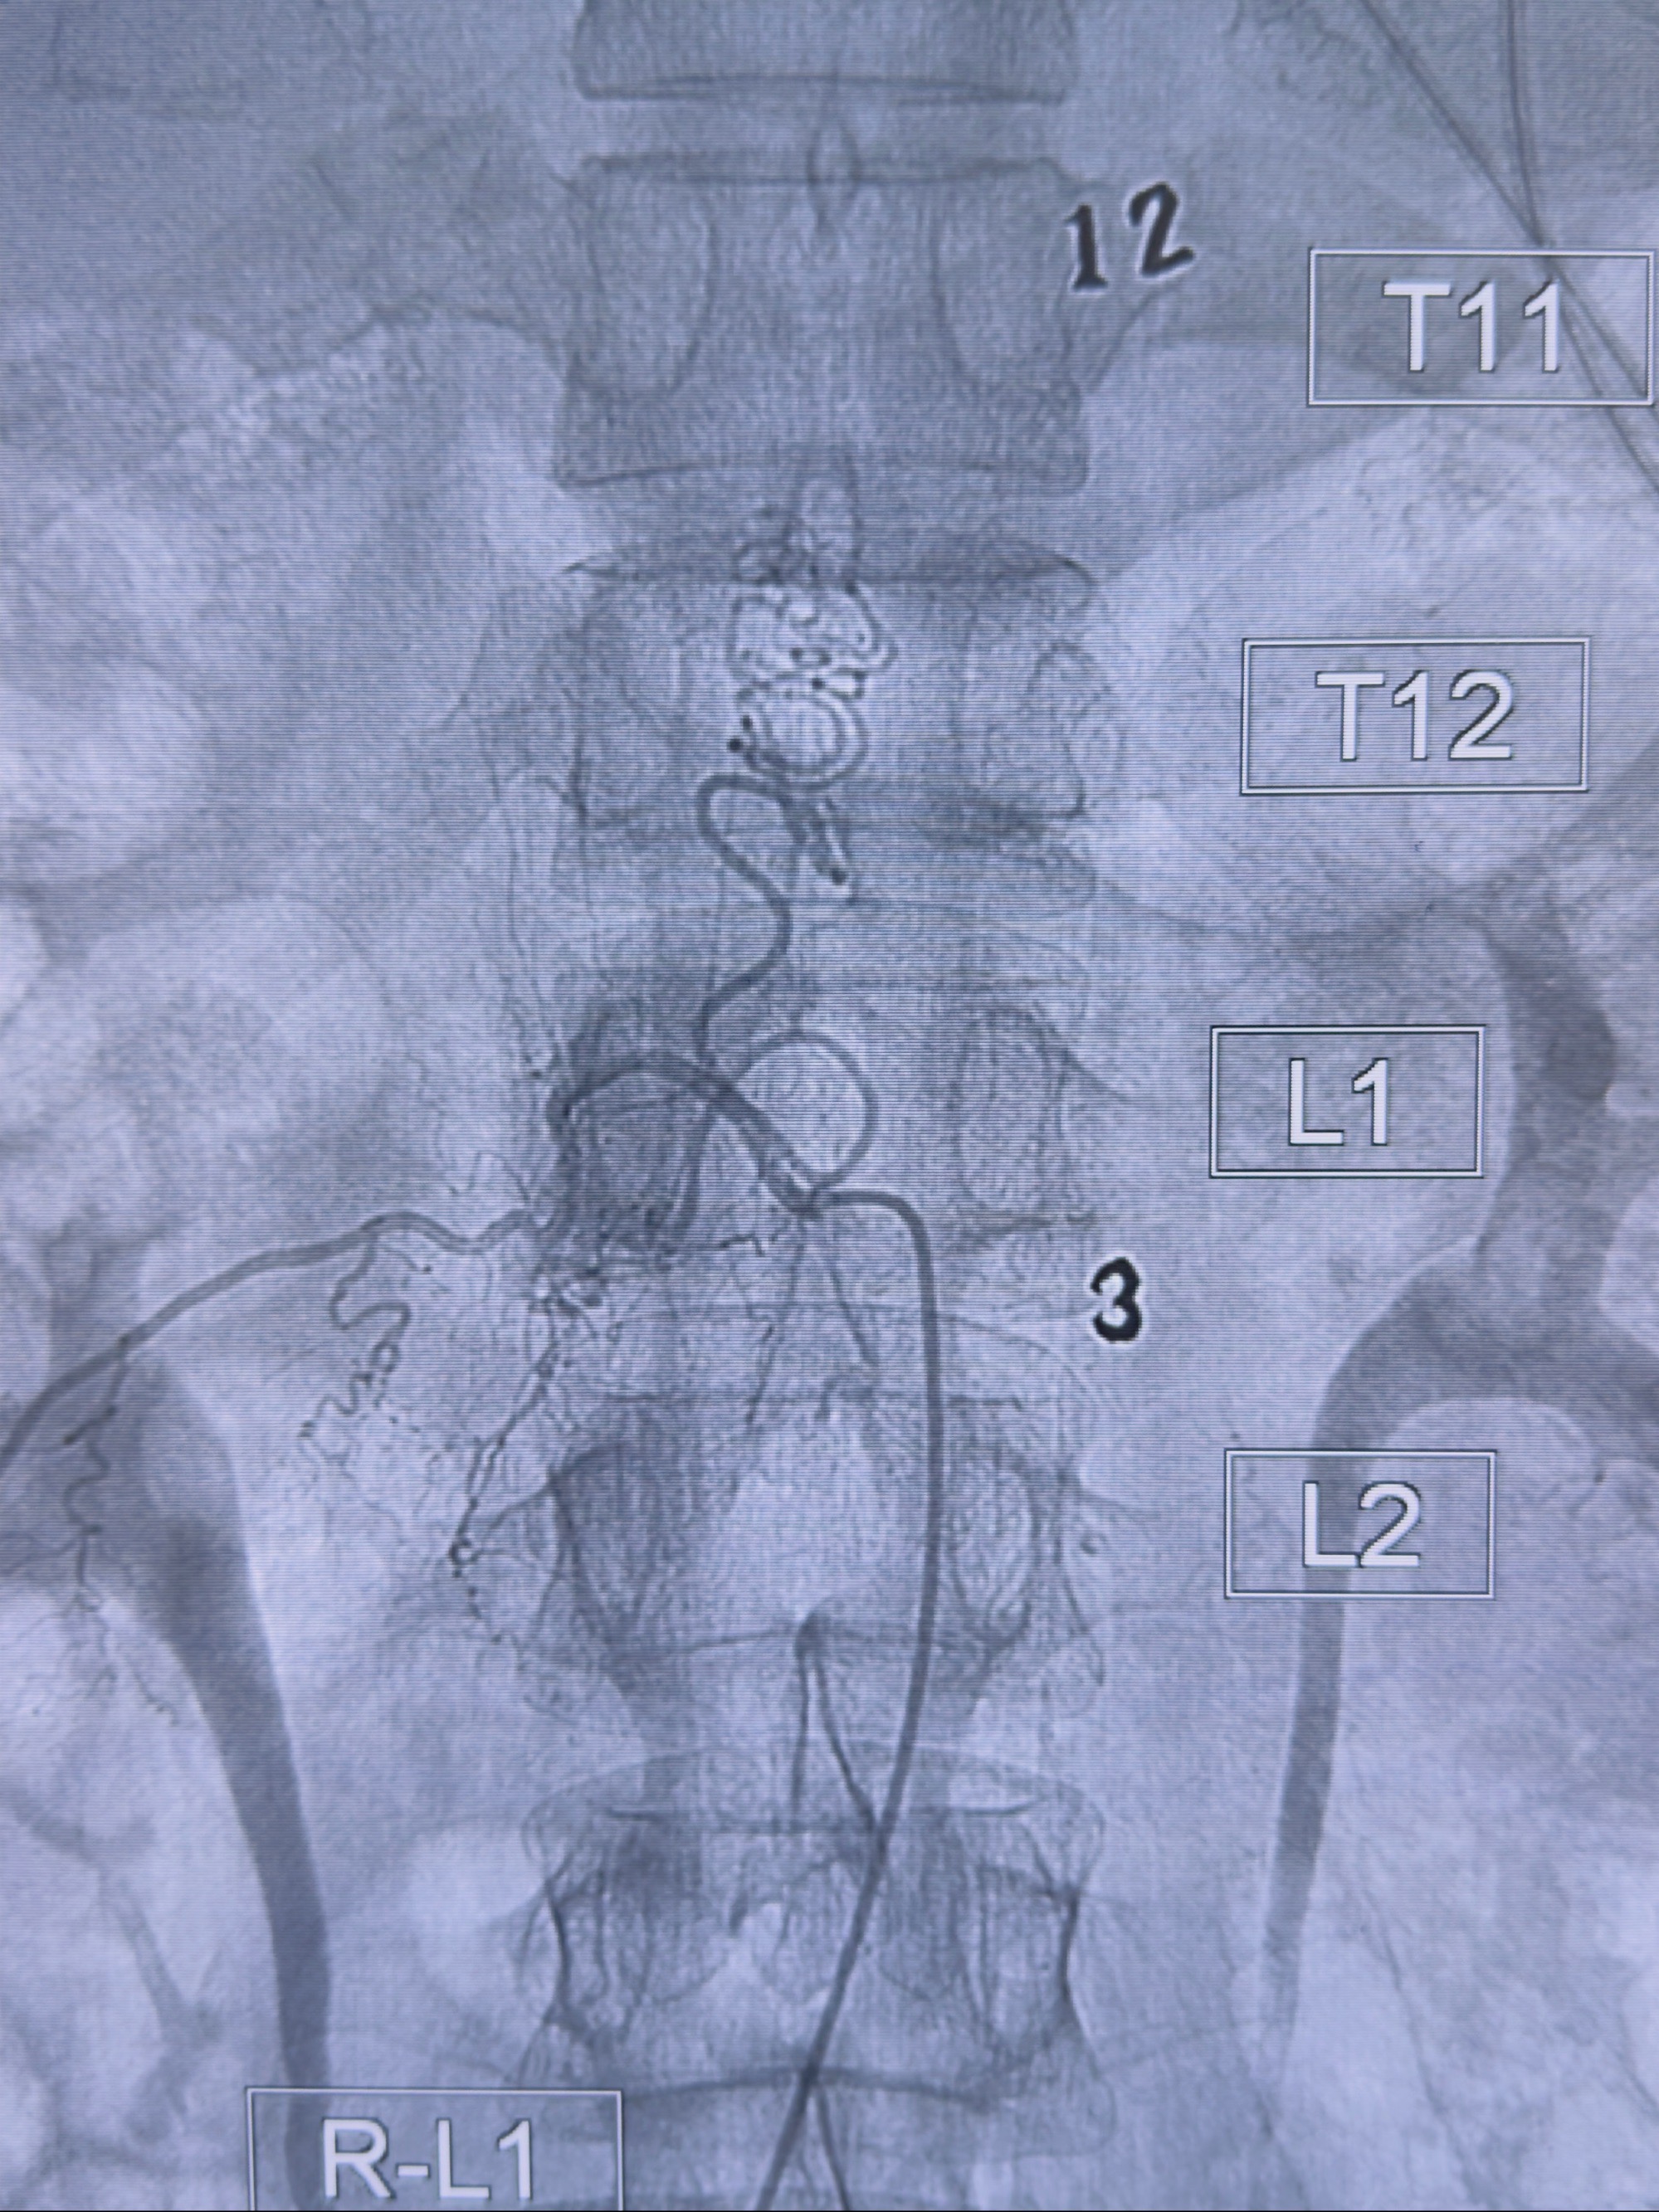

2023-10-13DSA:右侧L1水平硬脊膜动静脉瘘,供血动脉为右侧L1,附近动脉未见明确吻合供血,供血动脉处可见脊髓前动脉发出

1.建议外科手术,已行美兰定位c